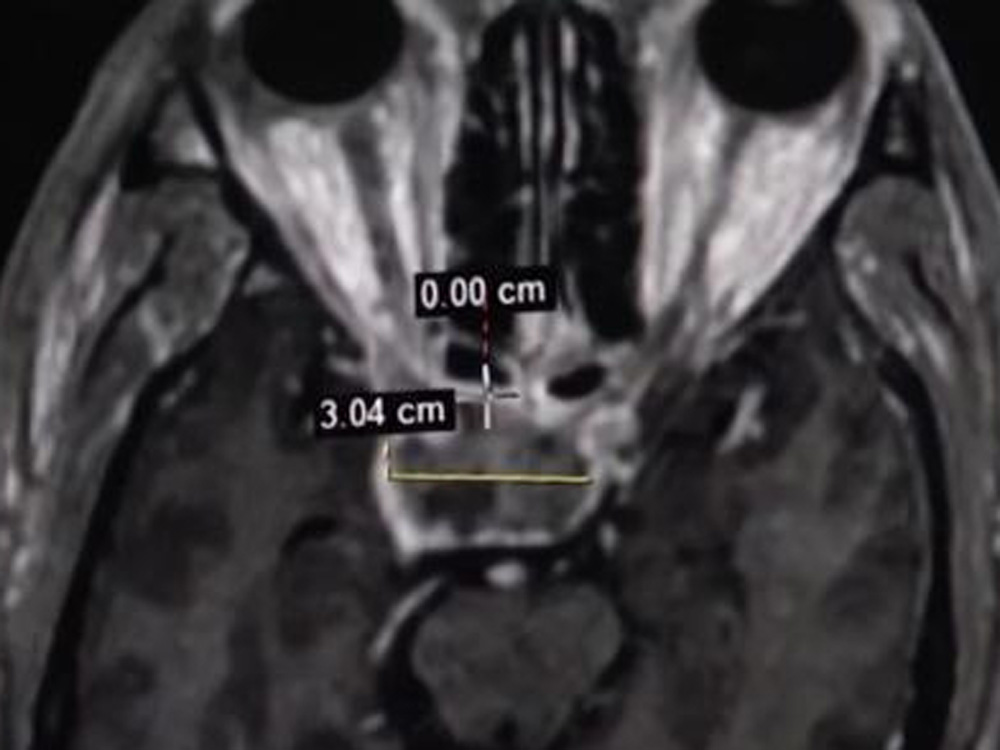

經過醫生嚴謹的問診和檢查,江坤被確診為生長激素型垂體瘤。在完善相關檢查後,醫生為他實施了垂體瘤切除手術。經過對症治療後,江坤於近日順利出院。做完手術之後,他原有的一些症狀,例如頭痛、眼瞼睜不開,這些臨牀症狀已經得到明顯改善,但他的面容、肢體肥大,以及心臟問題,這些損傷是不可逆轉的。

醫生表示,垂體是人體內分泌調節的「司令部」,垂體瘤是顱內常見的腫瘤。之所以會出現四肢、相貌改變等情況,主要是因為生長激素型垂體瘤導致生長激素過度分泌,從而出現四肢肥大症。